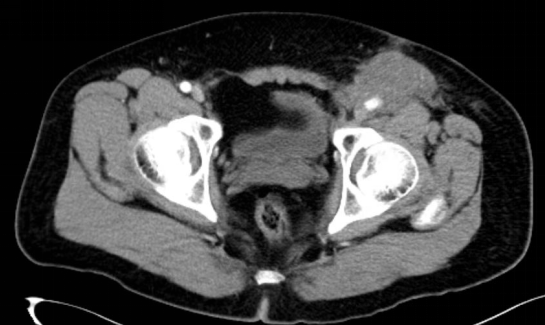

例1. 人工股血管置换技术保肢治疗左腹股沟复发软组织肉瘤